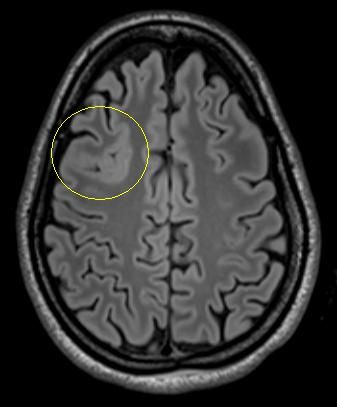

Es handelt sich um ein bildgebendes Verfahren, bei dem die Patienten in einer Röhre liegen und währenddessen mit Hilfe von wechselnden Magnetfeldern nach einem speziellen Epilepsie-Protokoll Bilder des Gehirns gemacht werden. So können Tumoren, Fehlbildungen oder andere Veränderungen des Gehirns, die Anfälle verursachen können, sichtbar gemacht werden. Durch moderne computergesteuerte Nachbearbeitungsmethoden oder Überlagerung mit anderen Bildmodalitäten können Läsionen dann noch besser dargestellt werden.

• Eine Gehirnläsion, die chirurgisch entfernt werden kann. Besonders wenn die Anfälle von einer umschriebenen Läsion (z.B. Tumor, Vernarbung, Fehlbildung) ausgehen, die chirurgisch gut entfernt werden kann, besteht eine hohe Chance auf Anfallsfreiheit.

Folgende Veränderungen oder Erkrankungen des Gehirns werden häufig und mit gutem Erfolg (70-80% Anfallsfreiheit) epilepsiechirurgisch behandelt:

Tumoren

Hippocampussklerose

Fokale

cortikale Dysplasie

Umschriebene Fehlbildungen der Hirnrinde